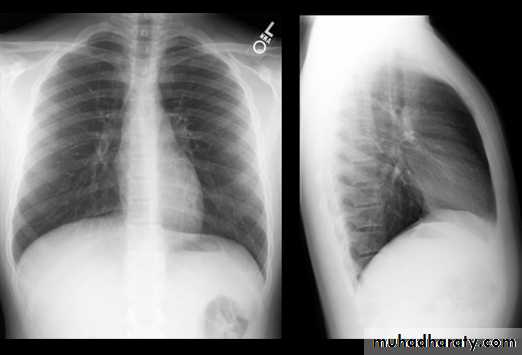

Normal chest XR PA & lateral view

Look carefully on both diaphragmatic cruse costo & cardio phrenic angles

8.normal chest XR PA & lat. view

9.normal radiologic anatomy of the chest